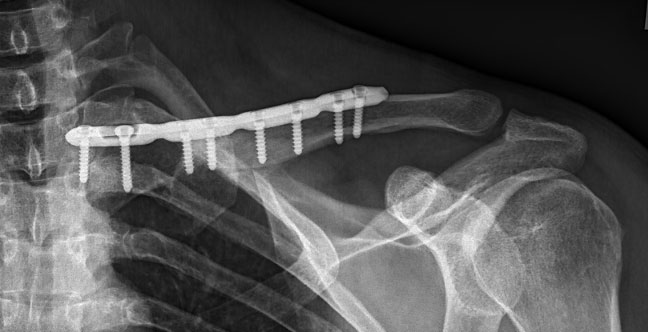

These images show clearly the deformity and shortening of the clavicle, and allow careful planning for a surgical procedure. After discussing his options with me, Joe decided to proceed with an operation to correct the malunited fracture. The first step of the operation was to re-break the clavicle at the site of the old fracture, allowing the bone to be brought out to its normal length. A plate and screws were inserted to hold the bone in its correct, anatomical position. A local bone graft was then used after collecting bone around the old fracture site to encourage healing of the old fracture ends.

X-rays taken after the operation showed good positioning of the clavicle, with normal length and alignment, as well as signs of bone healing. After 3 weeks of resting the arm in a sling, Joe’s shoulder function and range of movement was much improved, and he was able to return to many activities that had been difficult and painful before the operation.

During the surgery I made two separate cuts in the bone, allowing it to be repositioned and brought out to its correct length. The position of the cuts (or Osteotomy sites) were determined from his original fracture and from the 3D model. The newly aligned clavicle was held in place with a plate and screws, and excess bone was used as graft to stabilise the position and encourage healing of the bone. X-rays taken during and after the operation showed that the clavicle was back in its anatomical position.

X-rays taken during and after the operation showed that the clavicle was back in its anatomical position.